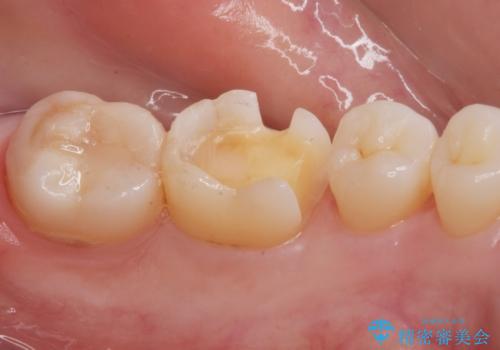

- 銀の詰め物が目立つので白くしたいとのことで来院。

拡大鏡下で銀の詰め物を除去して虫歯がない事を確認して

白い詰め物(e-maxインレー)にてやりかえを行いました。